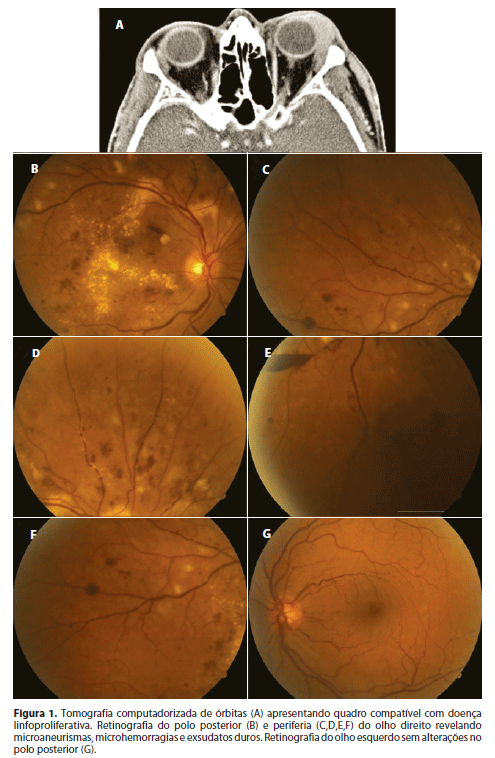

Paciente com 55 anos de idade, masculino, branco, diagnosticado com linfoma MALT orbitário à direita há três anos, submetido à radioterapia local (cerca de 35Gy em 25 sessões), há dois anos. Também havia sido submetido à cirurgia para exérese tumoral, há 2,5 anos. Atualmente, em quimioterapia, devido ao comprometimento da órbita contralateral. Paciente com queixa de redução progressiva da acuidade visual de olho direito (OD), há quatro meses, sem queixas sistêmicas. Apresentava diabetes mellitus tipo 2 há três anos, com bom controle glicêmico. Negava antecedentes oculares ou familiares dignos de nota. O paciente apresentava tomografia computadorizada (TC) de órbitas (Figura 1) revelando aumento de glândula lacrimal esquerda; obliteração de gordura extraconal; espessamento do músculo reto medial esquerdo; linfonodomegalias, quadro compatível com doença linfoproliferativa. Apresentava TC de crânio e tórax normais e TC de pescoço revelando linfonodomegalias nas cadeias jugulo-carotídeas. A biópsia incisional do tumor revelou linfoma de zona marginal extranodal (tipo MALT), corroborado pela imuno-histoquímica. O aspirado de medula óssea mostrou ausência de infiltração linfomatosa. A biópsia de corpo/antro gástricos revelou gastrite crônica moderada ativa com pesquisa para Helicobacter pylori negativa.

Ao exame oftalmológico, apresentava acuidade visual corrigida de conta dedos a 40 cm no OD e de 20/20 no olho esquerdo (OE); pressão intraocular (PIO) de 15/14 mmHg, biomicroscopia com catarata cortical anterior moderada, nuclear discreta e subcapsular discreta em OD e nuclear discreta OE, sem outras alterações. A fundoscopia do OD revelou microaneurismas, microhemorragias e exsudatos duros e, do OE, sem alterações no polo posterior (Figura 1).